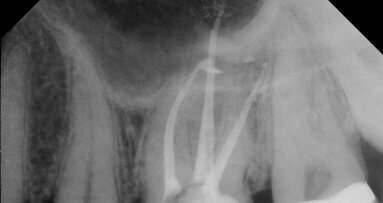

One of the most critical goals in implant therapy is the achievement of implant stability. In an upcoming webinar, Dr Barry P. Levin will present study findings on the importance of the insertion torque value (ITV) and the implant stability quotient (ISQ) for immediate implants, as well as preliminary findings of a study evaluating ITV and ISQ in grafted sites. Levin leads his own practice in Jenkintown in Pennsylvania in the US with a focus on implant dentistry and periodontics, and is a diplomate of the American Board of Periodontology. Prior to the online lecture, he provided Dental Tribune International with some details about his webinar.

SmartPeg attached in order to record ISQ for an immediate implant replacing tooth #11 prior to immediate temporisation. (Image: Barry P. Levin)

Dr Levin, what is ITV and what is ISQ? ITV relates to the amount of energy or force—measured in N cm—required to rotate a screw-shaped implant into its designated position. It is a measurement of rotational implant stability. It is a one-time measurement, only determined at the time of implant placement. ISQ is a value obtained by resonance frequency analysis. It measures the stiffness of the implant material, of the implant–bone interface and of the surrounding bone (trabecular and cortical ratio). ISQ measures the axial stability of the implant; it is non-invasive and repeatable.

Why are these two important for immediate implant placement? Both ITV and ISQ measure the level of implant stability. Because they measure two distinctly different aspects of stability, they are both of importance and should be considered critical when temporising or permanently restoring implants.